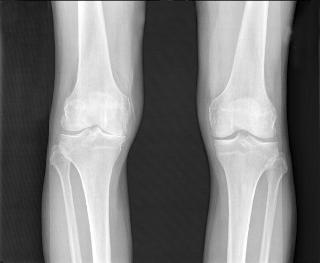

This is an X-ray image of osteoarthritic knees. (Credit:National Institute of Arthritis and Musculoskeletal and Skin Diseases (NIAMS))

"Patients are frequently in pain by the time osteoarthritis is diagnosed. The imaging tests most frequently used, X-rays, don't indicate the level of pain or allow us to directly see the amount of cartilage loss, which is a challenge for physicians and patients," said co-first author Averi A. Leahy, B.A., an M.D./Ph.D. student in the medical scientist training program at TUSM and the Sackler School.